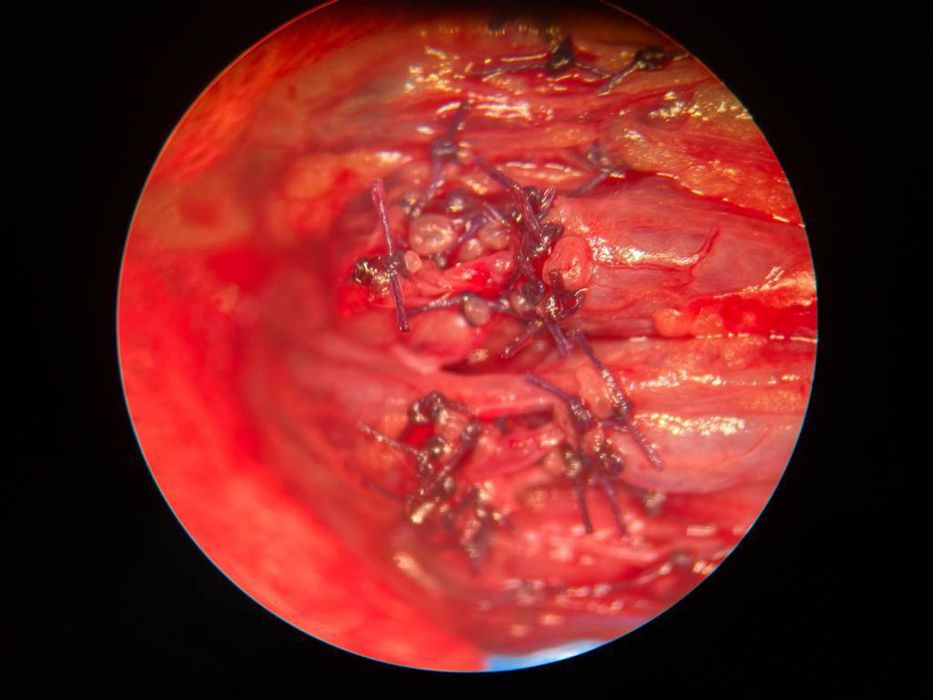

-Урологиялық-андрологиялық операциялар жасау